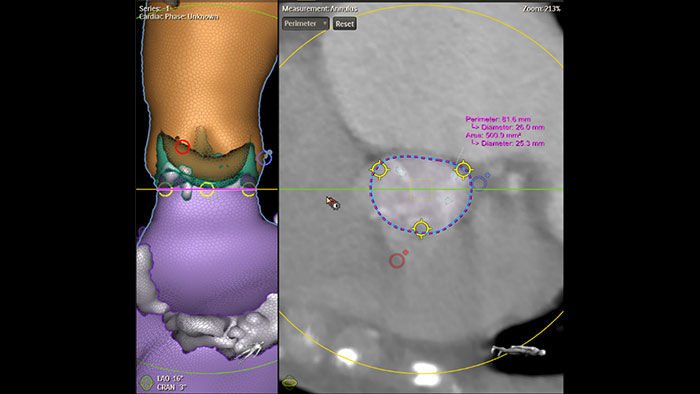

Dimensionamiento de la TAVR totalmente automatizado con HeartNavigator